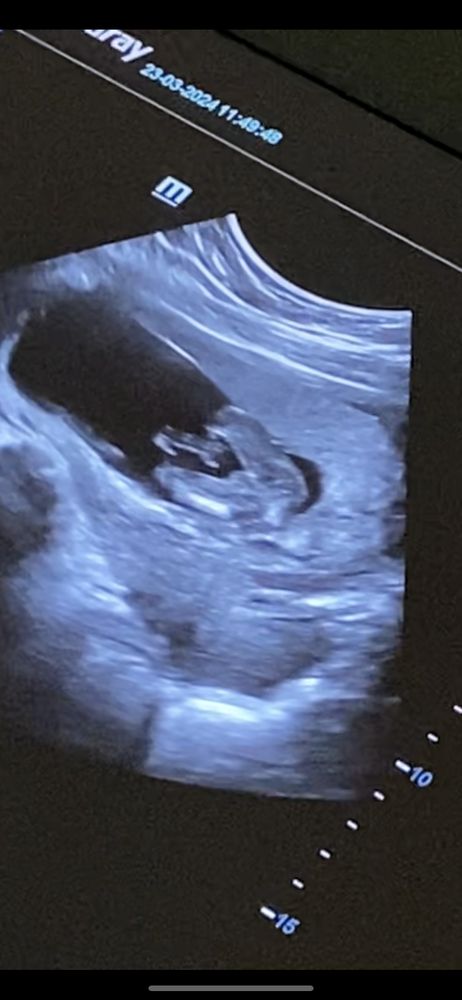

15 недель. Могли ли ошибиться с полом на узи?

Таня, вот и я не пойму( в одних ракурсах как будто между ножек ничего не торчит, а в другом ракурсе торчит, но как будто не совсем очевидно , что писюн Изображение Изображение Изображение

Дарья , ну вот даже по 1 фото. Таких больших и длинных стручков не бывает на этом сроке. У моих парней приличное хозяйства, но точно не такие были. Сомнительно все

Таня, вот и меня смущает, что как будто очень длинный.. буду ждать 2 скрининга теперь 🙏🏻 но надежда ещё есть на доченьку))

Вот на одном ракурсе явно я тоже вижу девочку как будто.. Изображение но вот при этом ракурсе врач сразу сказала, что как будто мальчик, писюн торчит

Светлана, хочется верить 🙏🏻 смущает просто, что на 3 фото врач показывала как будто писюн торчит.. а вот при другом ракурсе ( 1,2 фото) как будто вообще не видно никакого писюна